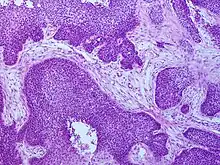

Cancers of the oropharynx primarily arise in lingual and palatine tonsil lymphoid tissue that is lined by respiratory squamous mucosal epithelium, which may be invaginated within the lymphoid tissue. Therefore, the tumour first arises in hidden crypts. OPC is graded on the basis of the degree of squamous and keratin differentiation into well, moderate or poorly (high) differentiated grades. Other pathological features include the presence of finger-like invasion, perineural invasion, depth of invasion and distance of the tumour from resection margins. Phenotypic variants include basaloid squamous carcinoma, a high grade form (see Chung Fig. 35-3(C)[28] and illustration here). They are most commonly non-keratinising. HPV+OPC also differs from HPV-OPC in being focal rather than multifocal and not being associated with pre-malignant dysplasia. HPV+OPC patients are therefore at less risk of developing other malignancies in the head and neck region, unlike other head and neck primary tumours that may have associated second neoplasms, that may occur at the same time (synchronous) or a distant time (metachronous), both within the head and neck region or more distantly. This suggests that the oncogenic alterations produced by the virus are spatially limited rather than related to a field defect.[29][28][30]

HPV+OPC is usually diagnosed at a more advanced stage than HPV-OPC,[8] with 75–90% having involvement of regional lymph nodes.[52] Furthermore, HPV+OPC is more likely to be poorly differentiated with nonkeratinized or basaloid cells.[53][54] [51]

Genetic signatures of HPV+ and HPV- OPC are different.[55][56][57][58][59] HPV+OPC is associated with expression level of the E6/E7 mRNAs and of p16.[60] HPV16 E6/E7-positive cases are histopathologically characterized by their verrucous or papillary (nipple like) structure and koilocytosis of the adjacent mucosa. Approximately 15% of HNSCCs are caused by HPV16 infection and the subsequent constitutive expression of E6 and E7, and some HPV-initiated tumors may lose their original characteristics during tumor progression.[61] High-risk HPV types may be associated with oral carcinoma, by cell-cycle control dysregulation, contributing to oral carcinogenesis and the overexpression of mdm2, p27 and cathepsin B.[62]